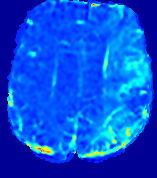

Figure 3: PIANO feature maps for one stroke patient, where the lesion is located in the left hemisphere. Top row: segmented stroke lesion region (white) on different slices, obtained from ISLES 2017. The corresponding slices for the PIANO feature maps are shown in the following rows.

For a better insight into an estimated velocity field 𝐕𝐕{\bf{V}} and diffusion field 𝐃𝐃{\bf{D}}, we compute the following maps: (1) 𝐕rgbsubscript𝐕𝑟𝑔𝑏{\bf{V}}_{rgb}: Color-coded orientation map of 𝐕=(Vx,Vy,Vz)T𝐕superscriptsuperscript𝑉𝑥superscript𝑉𝑦superscript𝑉𝑧𝑇{\bf{V}}=(V^{x},V^{y},V^{z})^{T}, obtained by normalizing 𝐕𝐕{\bf{V}} to unit length and mapping its 3 components to red, green, blue respectively; (2) 𝐕2subscriptnorm𝐕2\|{\bf{V}}\|_{2}: 222 norm of 𝐕𝐕{\bf{V}}; (3) D𝐷D: scalar field in Eq. 5.

Fig. 3 and Fig. 4 show the PIANO feature maps estimated from two ISLES 2017 patients: all are highly consistent with the lesion in both cases. Details of the blood flow trajectories are revealed in 𝐕rgbsubscript𝐕𝑟𝑔𝑏{\bf{V}}_{rgb} by the ridged patterns and the sharp changes of colors in the unaffected (right) hemisphere, while the flat patterns appearing within the lesion provide little directional information about the velocity and indicate low velocity magnitudes. Velocity magnitudes are more directly visualized via 𝐕2subscriptnorm𝐕2\|{\bf{V}}\|_{2}, from which one can easily locate the lesion where 𝐕2subscriptnorm𝐕2\|{\bf{V}}\|_{2} is low. D𝐷D also indicates lower diffusion values in the lesion, though with less contrast potentially due to the fact that it captures the accumulated effect of CA diffusion at the voxel-level.